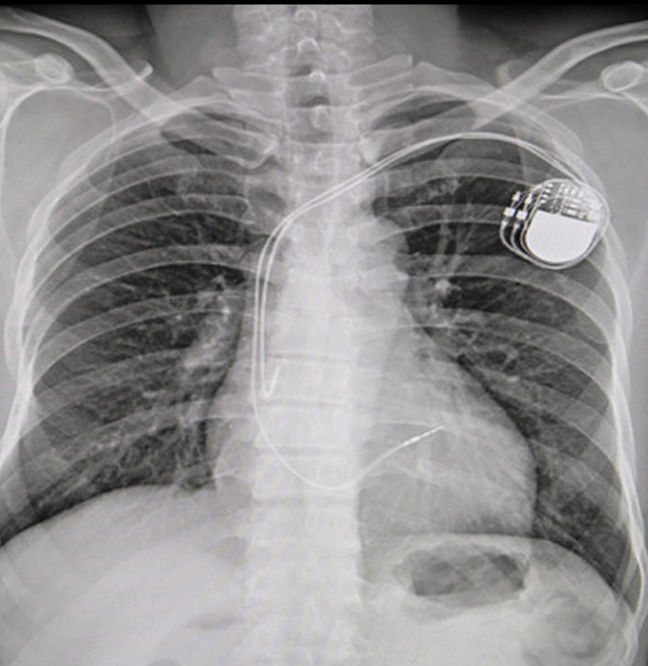

Implante de Marcapasos

Se emplea cuando existe enfermedad del sistema electrico del corazón, ocasionado que este lata de forma lenta, ocasionado síntomas como dolor de pecho, falta de aire, desmayos o crisis convulsivas.